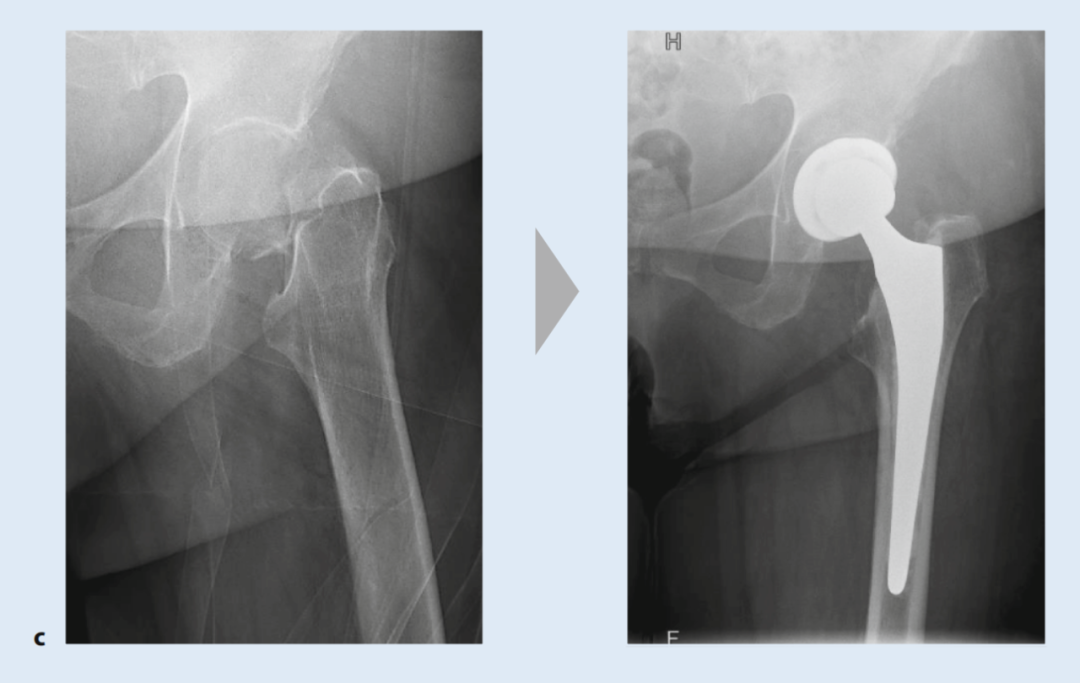

对于无移位股骨颈骨折,由于存在继发性移位风险以及需要数周制动,通常也建议手术治疗(图4)。根据一项荟萃分析的结果,绝大多数无移位骨折患者也能从手术稳定中获益。接骨术后的骨性愈合率为92.6%,而保守治疗下只有68.8%的骨折能够愈合。手术治疗的坏死发生率也较低(7.7% vs. 10.3%)。麻醉方式的选择(全身麻醉 vs. 区域麻醉)似乎对术后结果没有影响。

图4. 股骨颈骨折术前术后X光片(治疗方式对比):a) 螺钉内固定术,b) 双动头置换术,c) 全髋关节置换术